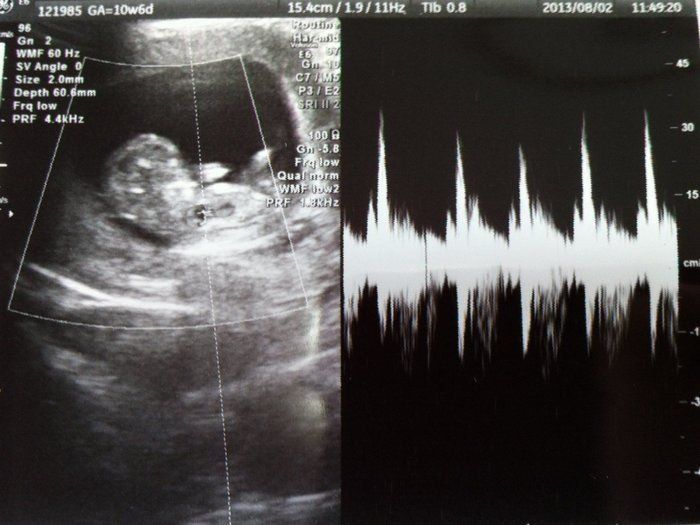

犬飼ねこさんの妊娠10週目のエコー写真

足が出来ました

へその緒が見えます。まだお腹に余裕があり動き回るころ